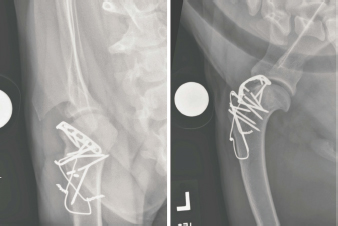

Open surgical reduction and stabilization (Vaughn, 1967; DeAngelis and Schwartz, 1970) was recommended. The dog was premedicated using dexdomitor 300 mcg IV and butorphanol 0.1 mg/kg IV, perioperative cefazolin was given at 30 mg/kg IV and continued Q 8 hours for 24 hours. Anesthesia was induced with 7.6 mg/kg Propofol given over 60–90 seconds to allow intubation, where anesthesia was maintained with Isoflurane. The left thoracic limb was clipped and prepared for aseptic surgery. The dog was positioned in dorsal recumbency and a craniolateral approach to the left scapulohumeral joint was done. During the initial stages of the procedure, the humeral head intermittently luxated cranially, predominately when the scapulohumeral joint was flexed. The acromial head of the deltoid and the sternocephalicus muscles were retracted and the infraspinatus, superficial pectoral, and deep pectoral muscles were incised and reflected to expose the joint capsule. The cranial joint capsule was circumferentially incised to expose the tendon of origin of the biceps brachii muscle and the transverse humeral ligament was incised. An osteotomy of the greater tubercle of the humerus was performed with an oscillating saw, allowing proximal reflection of the supraspinatus muscle. A pneumatic drill and burr were used to create a trapezoidal proximal-to-distal trough centrally in the exposed cancellous bone in the base of the osteotomy site. The trough was sculpted to conform to the dimensions of the bicipital tendon including the proximal myotendinous portion of the biceps brachii muscle (Fig. 2). The biceps brachii tendon was levered laterally into the trough using a Freer periosteal elevator and the humerus no longer luxated when the bicipital tendon was positioned in the trough (Fig. 3). The joint capsule was reopposed using 2-0 PDS placed in an interrupted cruciate pattern which prevented displacement of the tendon. To augment the stability afforded by the capsulorrhaphy, a six-hole 2.0 mm locking compression plate (DePuy Synthes, West Chester, PA) was placed along the craniolateral margin of the distal scapulohumeral joint line. The plate bridged the bicipital tendon and was secured to the humerus with three locking and one cortical 2.0 mm screws (Fig. 4). The greater tubercle was then repositioned on the incised surface of the humerus, 1 cm distal to the tubercle’s original location. The tubercle was secured with two 1.6-mm Kirschner wires and two strands of 18-gauge orthopedic wires placed in a figure-of-eight configuration as a tension band. Five additional 1.6-mm Kirschner wires were placed to further secure the tuberosity to the proximal humerus (Fig. 5). The remainder of the wound was closed in a routine fashion. After obtaining post-operative radiographs (Fig. 6), the left thoracic limb was placed in a Spica splint (DeCamp et al., 2016). Postoperatively, the dog was administered methadone (0.1 mg/kg IV Q 4 hours for two doses), transitioned to tramadol (3.3 mg/kg PO Q 8, beginning the morning following surgery), carprofen (16 mg/kg PO Q 12, beginning in the morning following the surgery), trazodone (3.3 mg/kg PO Q 8, beginning in the evening following the surgery), cefazolin continued (30 mg/kg IV Q 8 for 24 hours), transitioned to cephalexin (33 mg/kg PO Q 12, beginning in the evening following the surgery) and continued through discharge for 14 days.

Fig. 6. Caudocranial (left) and mediolateral (right) projection radiographs of the left scapulohumeral joint obtained immediately following the surgery. The scapulohumeral joint was congruent. A contoured locking compression plate was secured to the craniolateral articular margin of the proximal humerus. The plate was placed following joint capsule closure and bridged the transposed biceps brachii tendon. The greater tubercle was attached, but transposed 1 cm distally, and secured using multiple Kirschner wires and a figure-of-eight tension band wire.